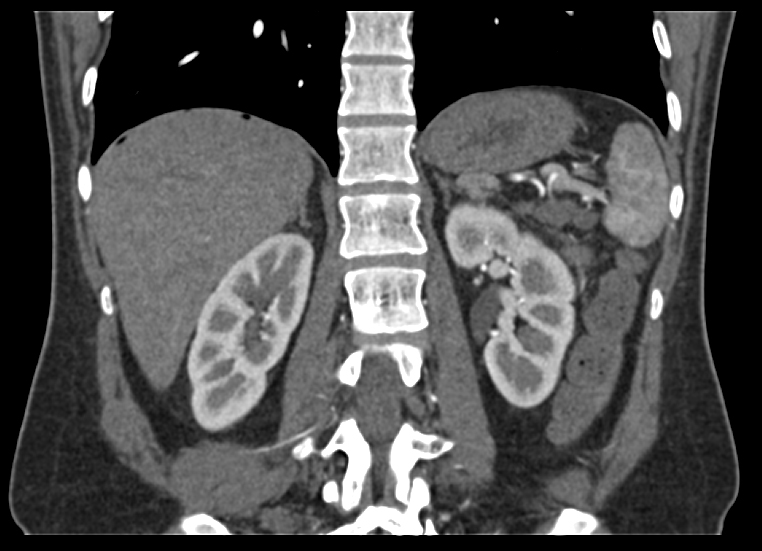

Компьютерная томография предоставляет врачам безошибочные данные о взаимном размещении органов, их структуре, а также наличии аномалий.

Процедуру проводят в амбулаторных условиях для исследования следующих органов:

- селезёнки;

- надпочечников;

- поджелудочной железы;

- печени, почек;

- желчного пузыря;

- сосудов брюшной полости и пр.

После обследования получают чёткие 2-х и 3-х-мерные снимки организма. Часто в этой процедуре применяют контрастирование с целью получить более качественные изображения. На них специалисты могут обнаружить опухолевые заболевания, их метастазы, цирроз печени, кисты почек, панкреатит, абсцессы органов и прочие болезни даже на ранних стадиях развития.